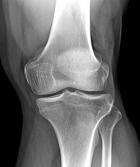

50 year old male with slowly enlarging mass medial left knee, first noticed six months ago

Zoom image: Radiological image Radiological image.